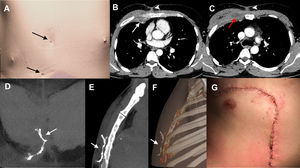

(A) 3D CT reconstruction image of the patient's body surface. Two cutaneous openings are clearly visible in the anterior thoracic wall (arrows). (B, C) Axial contrast-enhanced thoracic CT images (mediastinal window) at two different levels show inflammatory changes in the anterior chest wall: a collection in the right anterior pectoral muscles (red arrow), a small extrapleural collection adjacent to the right internal mammary vessels (white arrow), and several linear fistulous tracts extending toward the skin surface (arrowheads). (D–F) Thoracic CT reconstruction images (D, coronal maximum intensity projection [MIP]; E, sagittal MIP; F, sagittal 3D) after the administration of diluted iodinated contrast through two skin fistulous openings on the anterior chest wall demonstrate communication between the two openings and the absence of deep soft tissue extension (arrows). (G) Post-surgical image of the anterior chest wall after the resection of the fistulous tract and the utilization of a vascularized muscle flap.

We present the case of a 31-year-old male with X-linked CGD, on chronic antibiotic treatment, with a long-standing medical history of infections (pulmonary and soft-tissue) and recurrent thoracic and abdominal fistulas, who presented complaining of inflammation of the chest wall. The patient had undergone multiple surgical interventions in the past, including a right middle lobectomy for pulmonary aspergillosis and surgical debridement for soft-tissue infections. On physical examination, two small fistulous orifices through which fluid material was draining (Fig. 1A) were found in the anterior chest wall, with doubts about the extent in depth of the inflammatory changes. A contrast-enhanced thoracic computed tomography (CT) confirmed the existence of inflammatory changes in the anterior chest wall (Fig. 1B, C) but ruled out the presence of pulmonary consolidations or pleural fluid collections.

The decision was made to perform a CT-fistulography using iso-osmolar iodinated contrast (iodixanol 320mg/mL, diluted to 25% with saline) through the two cutaneous fistulous openings, due to its excellent anatomical and contrast resolution. CT-fistulography revealed a subcutaneous communication between the two orifices, ruled out involvement of deeper tissues (Fig. 1D–F) and aided the thoracic and plastic surgery teams in planning the resection of the fistulous tract and the reconstruction of the anterior chest wall (Fig. 1G).